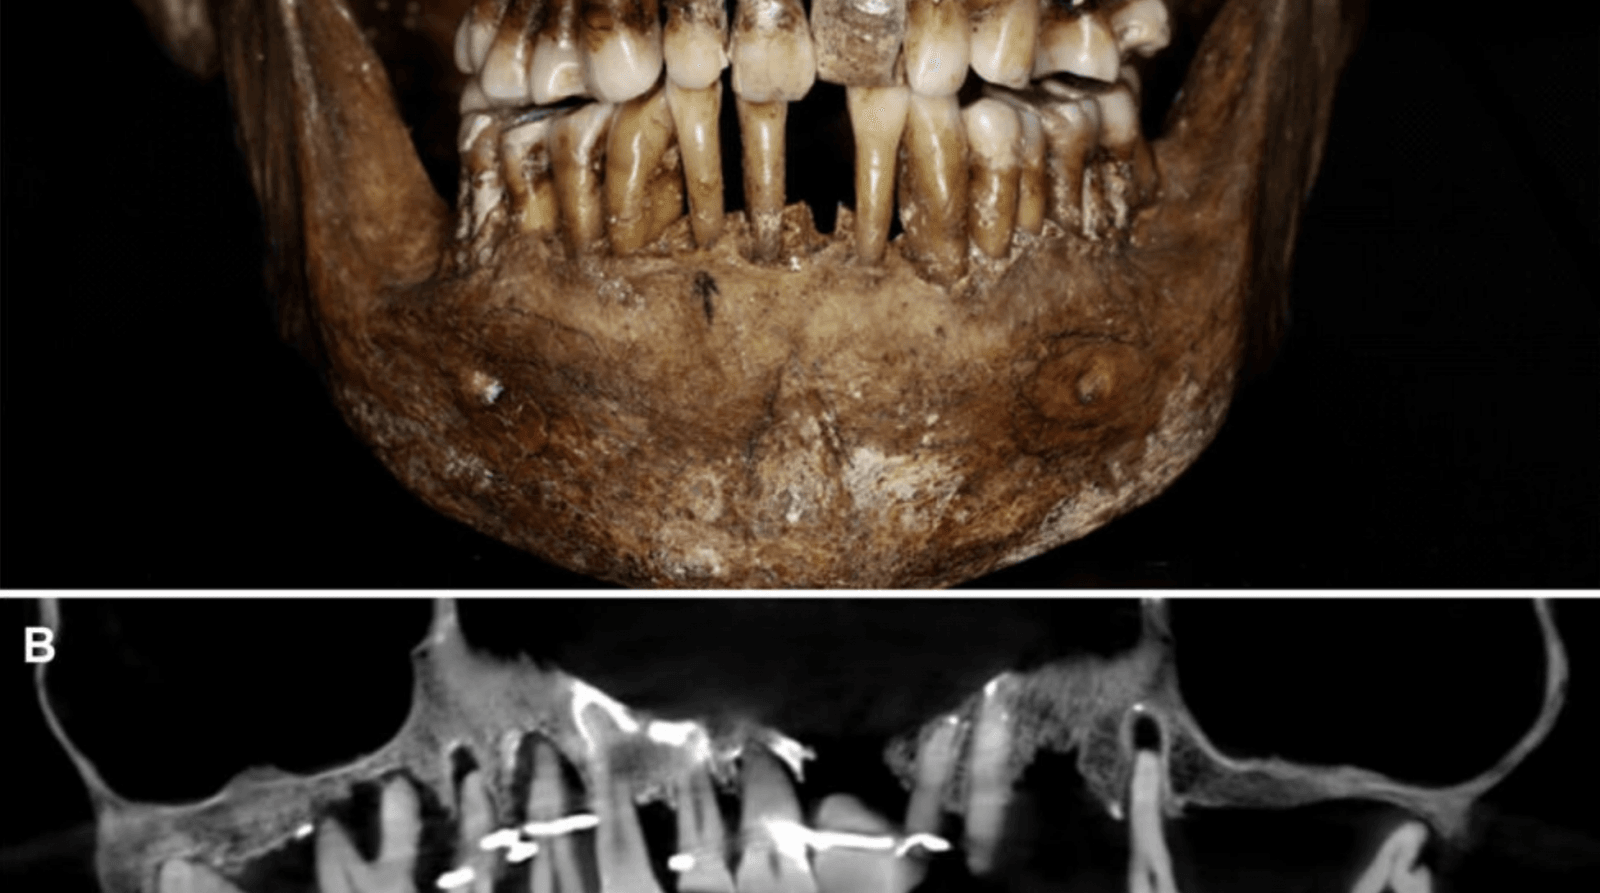

Wykorzystując stożkową tomografię komputerową, wykazano, że złoty drut został użyty do utrzymania razem i zaciśnięcia kilku zębów. Arystokratka miała również sztuczny ząb wykonany z kości słoniowej, a nie z kości hipopotama, co było popularne w tamtych czasach.